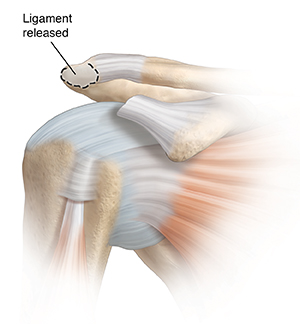

The type of surgery you have depends on your shoulder problem. Surgery can remove the bursa if it is swollen. If the coracoacromial ligament is tight, it may be released. If the acromion is hooked or has bone spurs, a part of it may be taken out. Before surgery, you’ll be given medicine to keep you free from pain. There are 2 different types of surgery. These are:

| A tight coracoacromial ligament may be released. |